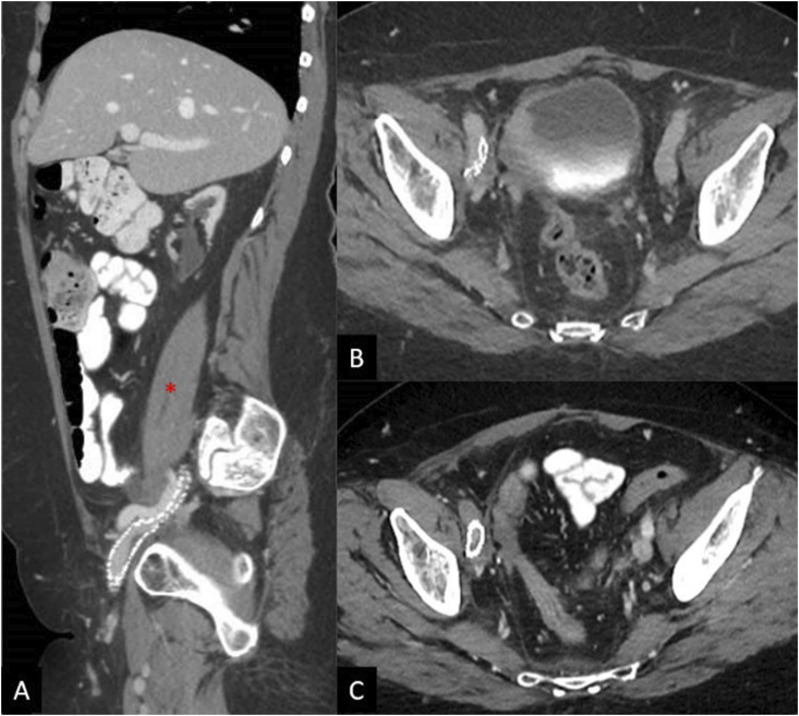

回腔静脉血栓形成和流出梗阻是一种有许多可能原因的疾病,通常表现为与静脉充血或不全有关的症状。最近的设备发展和血管内支架置入术和静脉成形术对生活方式限制症状的可用性难以保守治疗,导致对这些手术的兴趣增加。虽然静脉支架置入的几种常见并发症已经有了很好的描述,但一种罕见和紧急的并发症是附近动脉压迫或闭塞。在此,我们报告2例髂静脉再通和支架置入后发生髂动脉闭塞的病例,并讨论可能导致这种罕见并发症的因素。

Ileocaval venous thrombosis and outflow obstruction is a condition with many possible causes that typically presents with symptoms related to venous congestion or insufficiency. Recent device development and availability of endovascular stenting and venoplasty for lifestyle-limiting symptoms refractory to conservative management has led to increased interest in these procedures. While several common complications of venous stent placement have been well-described, 1 uncommon and emergent complication is nearby arterial compression or occlusion. Here we present 2 cases of iliac artery occlusion occurring after iliac venous recanalization and stenting, and discuss possible factors that may contribute to this uncommon complication.